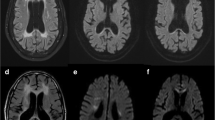

Diffusion-weighted imaging findings in Zellweger disease are rather unremarkable. The extensive hypointensities within the cerebral hemispheres correspond to non-myelinated white matter, consistent with severe retardation of the myelination process, without any evidence of active demyelination (Fig. 7). Diffusion tensor imaging findings in patients with Zellweger syndrome show reduced fractional anisotropy and elevated apparent diffusion coefficient values compared to age-matched controls [10, 26]. The fractional anisotropy changes are believed to indicate the lack of myelination of the fiber tracts, whereas the ADC value abnormalities may be related to the concomitant increase of free water diffusion within the extracellular space.

MR imaging findings in a 6-month-old female infant with Zellweger disease. Axial T1-weighted fast inversion recovery (a), diffusion-weighted (b) and ADC map (c) images. Poor overall myelination is seen on the inversion recovery image with some myelin shown within the internal capsules and the optic radiations only. The diffusion-weighted (b=1,000 s) and ADC map images do not provide evidence of active demyelination, but suggest lack of the physiological anisotropy in the peripheral white matter structures, consistent with severely delayed and hypomyelination